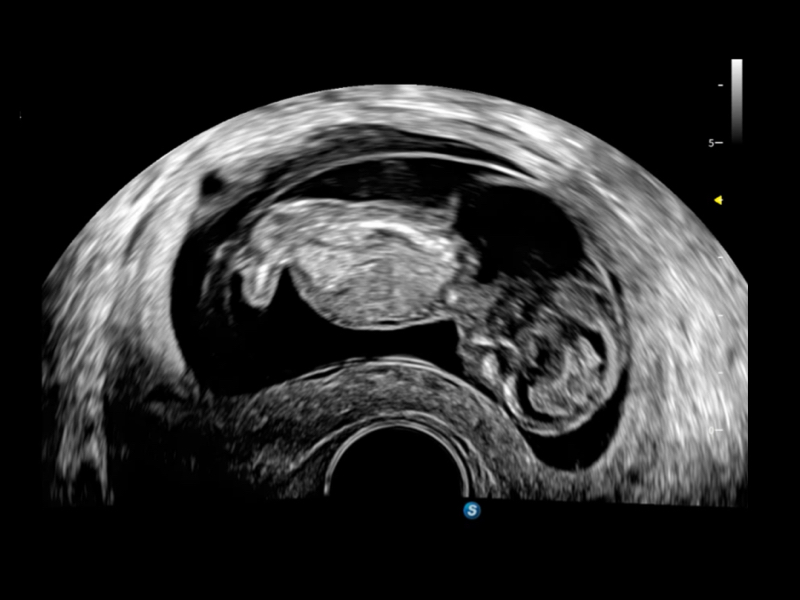

• S-Live Studio liefert eine brillante, realistische Hautvisualisierung in Echtzeit, indem es die Lichtausbreitung auf der Hautoberfläche simuliert und so die Tiefe und Authentizität des dreidimensionalen Bildes bereichert.

• One-Stop-Lösung zur automatischen Standard-Flugzeugerfassung und -messung. Mit nur einem Klick werden 29 Standardabschnitte von fetalen Ultraschallbildern intelligent identifiziert, und 13 biometrische Messungen werden automatisch mit hoher Intelligenz, Genauigkeit und Effizienz erfasst, um eine beispiellose Leichtigkeit während des Betriebs zu ermöglichen.